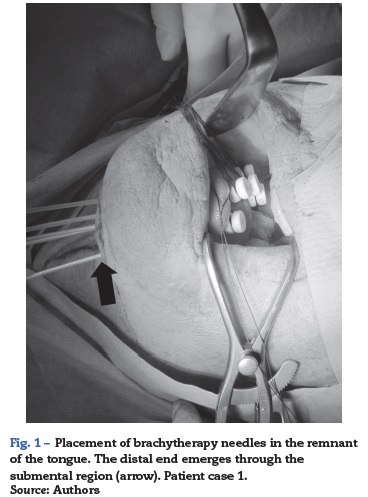

These oral brachytherapy techniques require placing some needles across the affected area to connect then to the radiation source using external probes (Fig. 1). Evidently, these procedures require general anesthesia with endotracheal intubation to facilitate the job of cancer radiotherapists and maxillofacial surgeons.